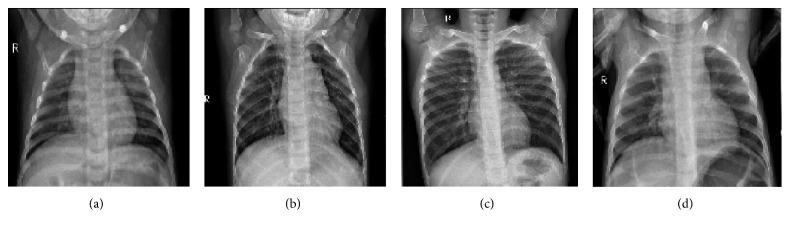

This study proposes a convolutional neural network model trained from scratch to classify and detect the presence of pneumonia from a collection of chest X-ray image samples. Unlike other methods that rely solely on transfer learning approaches or traditional handcrafted techniques to achieve a remarkable classification performance, we constructed a convolutional neural network model from scratch to extract features from a given chest X-ray image and classify it to determine if a person is infected with pneumonia. This model could help mitigate the reliability and interpretability challenges often faced when dealing with medical imagery. Unlike other deep learning classification tasks with sufficient image repository, it is difficult to obtain a large amount of pneumonia dataset for this classification task; therefore, we deployed several data augmentation algorithms to improve the validation and classification accuracy of the CNN model and achieved remarkable validation accuracy.

本研究提出了一种从头开始训练的卷积神经网络模型,用于从胸部 X 射线图像样本集中分类和检测肺炎的存在。与其他仅依赖迁移学习方法或传统手工技术来实现出色分类性能的方法不同,我们从头开始构建了一个卷积神经网络模型,从给定的胸部 X 射线图像中提取特征,并对其进行分类,以确定一个人是否感染了肺炎。该模型有助于缓解处理医学图像时经常面临的可靠性和可解释性挑战。与其他具有足够图像库的深度学习分类任务不同,很难为这个分类任务获得大量的肺炎数据集;因此,我们部署了几种数据增强算法来提高 CNN 模型的验证和分类准确性,并取得了显著的验证准确性。